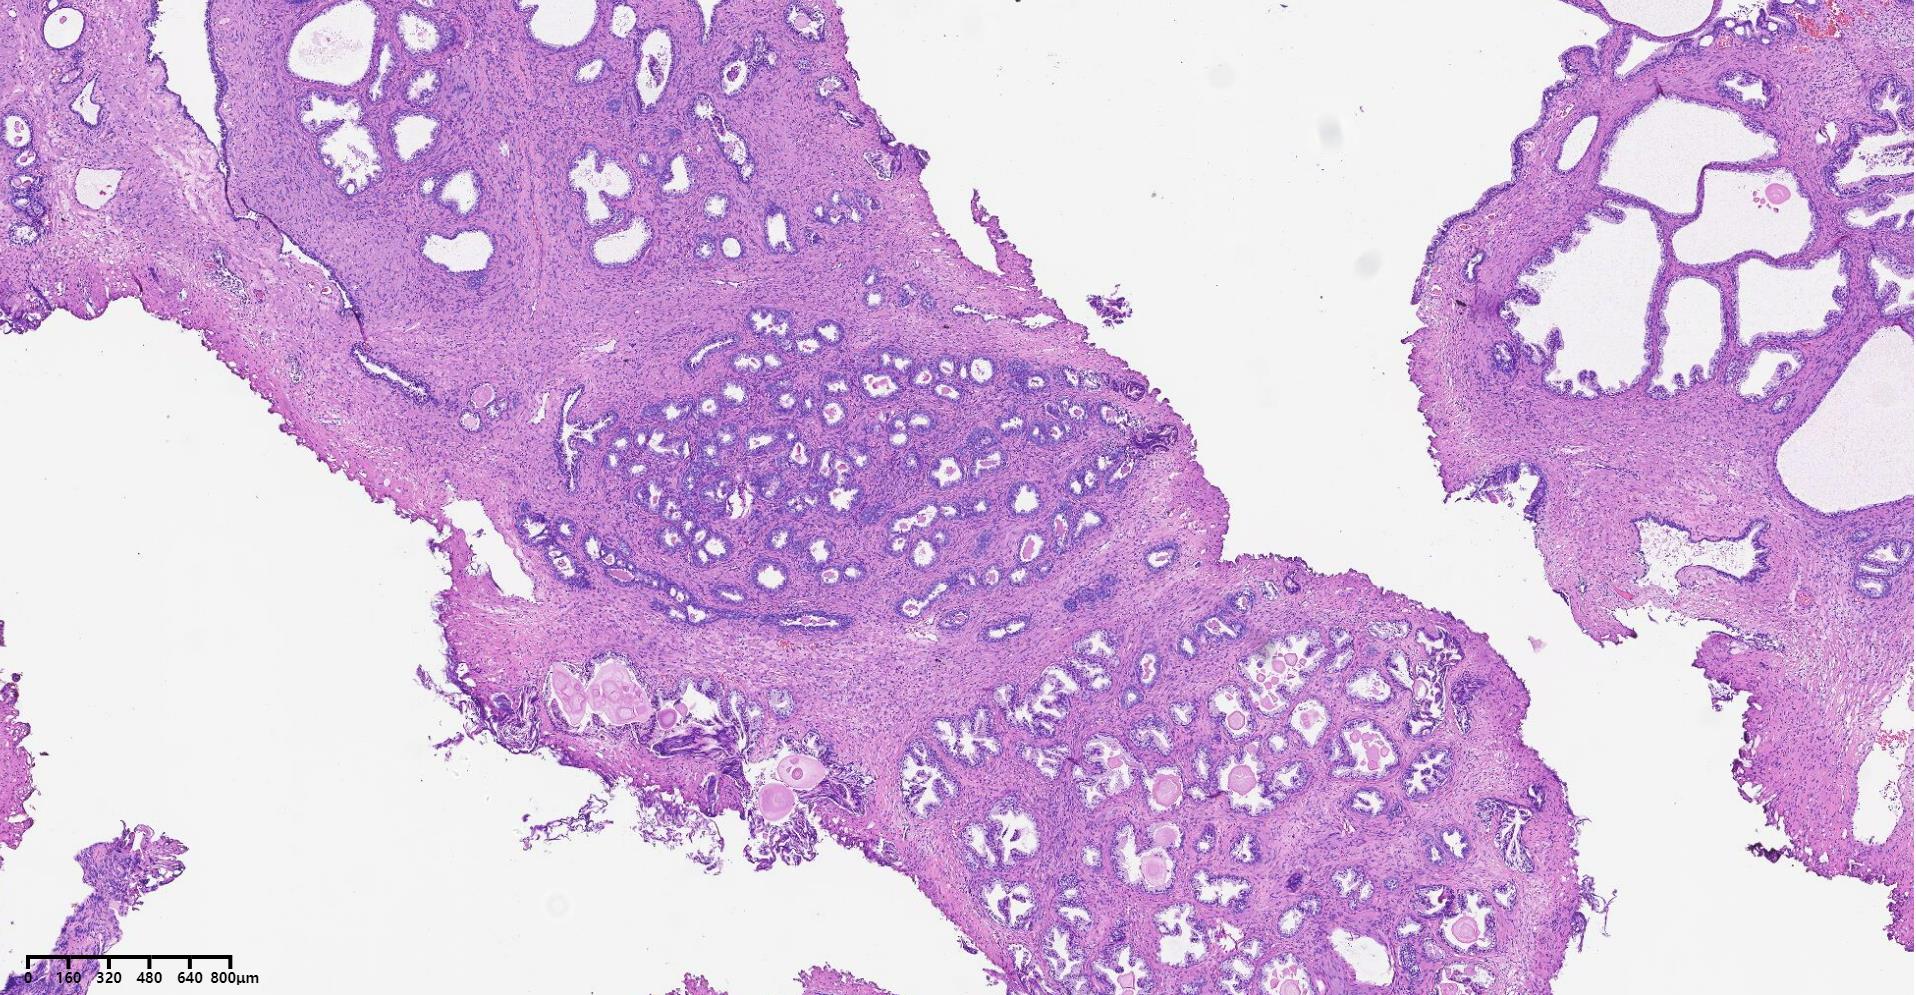

前列腺PIN?

性别

男

年龄

79岁

临床诊断

一般病史

发现肉眼血尿5月余,PAS 5.7

标本名称

经尿道前列腺等离子电切组织

大体所见

碎软组织一堆,共直径5.2

图1

BPH.

本例核仁巨大,值得关注!

嗜酸性大核仁,胞浆透亮,PIN没问题。还是组化一下吧,